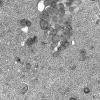

BASIC PROCESSES

Neuroaxonal dystrophy (2)